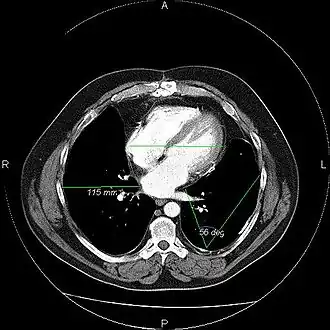

Picture Archiving and Communication System, afgekort als PACS, is een beeldverwerkend systeem (computers en servers in een netwerk met specifieke software) dat het mogelijk maakt om via computers de digitale beelden (met verslag) gemaakt op de afdeling radiologie, te verwerken, te archiveren en te verspreiden bij de aanvragende medisch specialisten.

Het PACS is een applicatie primair bedoeld voor de radioloog. Maar door het digitale karakter van het systeem is het ook mogelijk dat anderen dan radiologen toegang hebben of krijgen tot de digitale PACS-beelden. In het PACS worden alle digitale radiologische beelden volgens een speciaal protocol, DICOM, opgeslagen die zijn geacquireerd op de modaliteiten (of radiologietoestellen). Middels standaardkoppelingen, zoals HL7, worden de juiste patiëntengegevens van het ZIS (Ziekenhuis Informatie Systeem) naar het PACS gestuurd. Er zijn PACS-systemen die volledig zijn geïntegreerd met het RIS (radiologie informatiesysteem). Door deze PACS-RIS-koppeling ontstaat er een complete radiologische workflow waarbij de juiste patiëntengegevens (uit het ZIS) met de juiste beeldgegevens worden gekoppeld. Op het secretariaat worden de afspraken van de patiënten in een lijst gezet. De verschillende modaliteiten (röntgenapparaat, MRI-scanner, CT-scanner, e.d.) kunnen hun eigen werklijst (de zogenaamde DICOM Modality Worklist, oftewel DMWL) opvragen, hierdoor is er een vlotte doorstroming van alle informatie naar de modaliteiten, dokters en verpleegkundigen, waardoor: